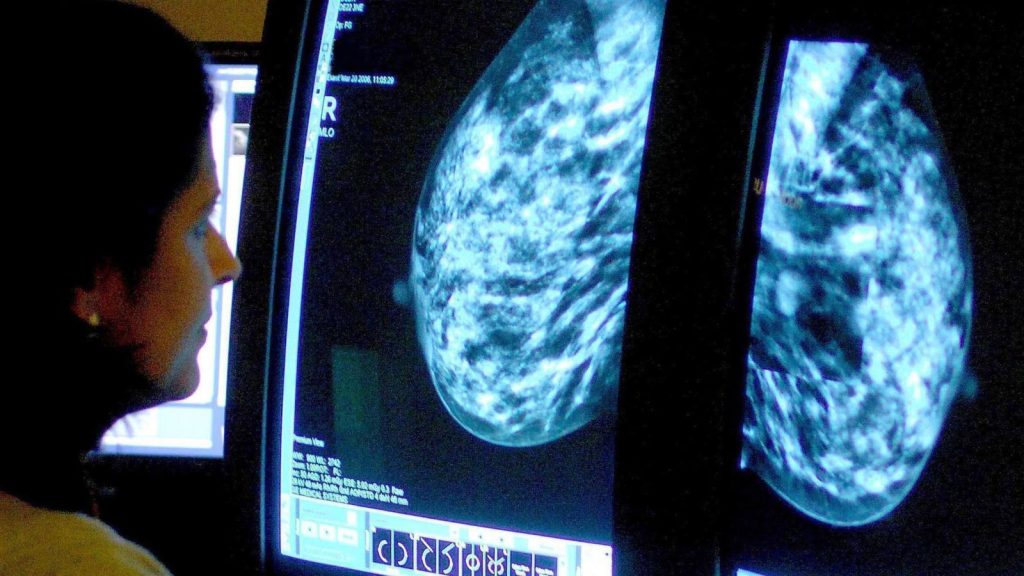

Preventative treatment designed to stop the recurrence of breast cancer can actually cause the cancer cells to mutate and ‘hibernate’, only to grow again years later, according to new findings.

Researchers who set out to explain why breast cancer can return years after initial treatment have found that hormone therapies, used to prevent breast cancer from recurring, can trigger changes in some cells.

These changes cause the cells to lie dormant instead of dying off, and the cells then “wake up” years later, causing a relapse that is harder to treat.

But the study found there may be a way to target these “sleeping” breast cancer cells before they “wake up”, offering new hope for patients with oestrogen receptor positive (ER+) breast cancer – which makes up 80% of all breast cancers.